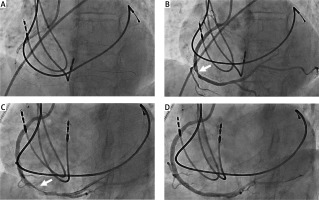

A 71-year-old woman was admitted to our institution for an ongoing inferior ST-elevation myocardial infarction (STEMI). TIMI 3 flow of a mid-right coronary artery (RCA) thrombotic occlusion was restituted with balloon angioplasty (Sapphire II NC 3 × 15 mm, OrbusNech) and stenting at 9 atm (Ultimaster Tansei 3.5 × 28 mm, TERUMO) (Figure 1 A). Post-stenting angiogram revealed a distal stent edge stenosis which was not restituted after intracoronary nitroglycerin excluding vasospasm (Figure 1 B). Moreover, this lesion was evolutive: the stenosis aspect and degree became worse. As the dissection mechanism was suspected, we treated this lesion with a second stent. While stenting, we observed a distal migration of the sub-intimal contrast dye that made us think about a probable iatrogenic hematoma extension. A tight distal RCA stenosis was revealed on angiogram with clear subintimal dye trapping and extraluminal compression while the patient had recurrence of chest pain and inferior ST-segment elevation (Figure 1 C). The diagnosis of iatrogenic subintimal hematoma defined as blood accumulation in the medial space without distinguishable entry or exit points was considered [1]. We thought that additional stenting could worsen the situation by moving forward the hematoma and jeopardize the RCA crux and its distal flow. Intracoronary imaging would have confirmed the diagnosis but was not performed in the context of emergency so as not to delay revascularization. Hence, we decided to fenestrate this hematoma with a cutting balloon (CB) angioplasty in order to evacuate blood from the subintimal space as previously described for spontaneous hematoma [2]. At the site of hematoma, three CB (Wolverine 3 × 10 mm, Boston Scientific) incremental inflations at 6, 8 then 11 atm were required to obtain the awaited effect and recover a good flow without subintimal contrast trapping anymore. Chest pain and ST elevation disappeared immediately; nevertheless, we stented this fenestrated area (Ultimaster Tansei 3.5 × 28 mm, TERUMO) (Figure 1 D). Ultra-sensitive troponin maximum level was 237 594 ng/l and the patient was discharged from hospital after 5 days with a limited inferior wall akinesia on echocardiography. Frequently, after stent implantation when stenosis appears at the stent edge, diagnosis and management of such an issue is difficult. In some exceptional situations when true lumen compression leads to ischemia, cutting balloon angioplasty at the site induces a fenestration between the true lumen and hematoma. This situation has been described in cases of spontaneous coronary artery dissection or during chronic total occlusion revascularization [3, 4]. In the context of ventricular arrhythmias or clinical instability as in our case, diagnosis should be confirmed by intracoronary imaging: intravascular ultrasound (IVUS) or optical coherence tomography (OCT), even though OCT risk is a distal propagation of the hematoma. To fenestrate the hematoma while minimizing the risk of distality extension, a size ratio of 1 : 1 cutting balloon to artery diameter ratio at nominal pressure should be recommended. Nevertheless, CB inflation pressure could be increased to rated burst pressure until obtaining the awaited effect as in our example. We could also advocate increasing CB size in case of failure to obtain fenestration. Some case reports have described successful angioplasty without stenting. In our case, the high thrombotic burden and close location to the RCA bifurcation led us to stent this wounded area. Coronary intra-mural hematoma during STEMI percutaneous intervention revascularization is a rare complication. Here we report a case to illustrate an indication for cutting balloon on post-stenting intramural hematoma during STEMI.

Figure 1

A – Coronary angiogram showing mid-RCA occlusion just before balloon angioplasty. B – Persistent significant stenosis at the stent edge did not resolve with intracoronary nitroglycerin. C – Post-stenting angiogram exhibiting propagation of compressive intramural hematoma. D – Final result showing successful angioplasty